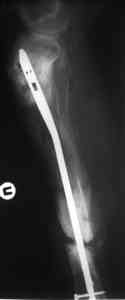

Пример (пациент 46 лет, лечился у нас 4 года назад, внутренний остеосинтез выполнен с определенными погрешностями, но перелом сросся и рецидива инфекции не было): рис. 1,2 - при переводе к нам в институт, рис. 3 - после микрохирругической пластики, рис. 4, 5 - после интрамедуллярного остеосинтеза, рис. 6, 7, 8 - внешний вид и рентгенограммы после окончания лечения

Штифт лучше взять неканюлированный, диаметр 10-11 мм. с большим количеством отверстий для блокирования (лучше ввести все блокирующие винты для создания максимальной стабильности).

Больному была выполнена операция. после демонтажа аппарата Илизарова столкнулись с "прямо на глазах" сокращением регенерата. Гвоздь сквозь регенерат удалось провести без технических трудностей. Сложности были с репозицией отломков, что связано с выраженным остеопорозом, их короткими размерами. Пришлось применить полер-винт. Выполнили блокирование. По причине укорочения регенерата пришлось повторно смонтировать аппарат Илизарова и начать транспорт фрагмента на гвозде (14 мм). Больному разрешена ходьба с дозированной нагрузкой на больную ногу. Контрольные рентгенограммы прилагаются. Нынешняя ситуация породила ряд вопросов и замечаний: